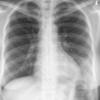

Case 2 Lingular pneum PA

Date: 04/17/2005

Views: 6409